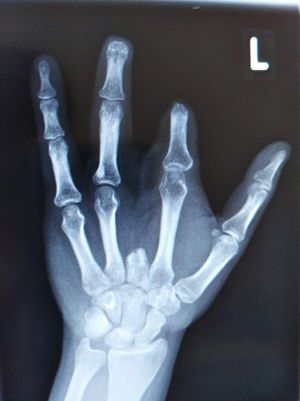

Accident with an electric saw